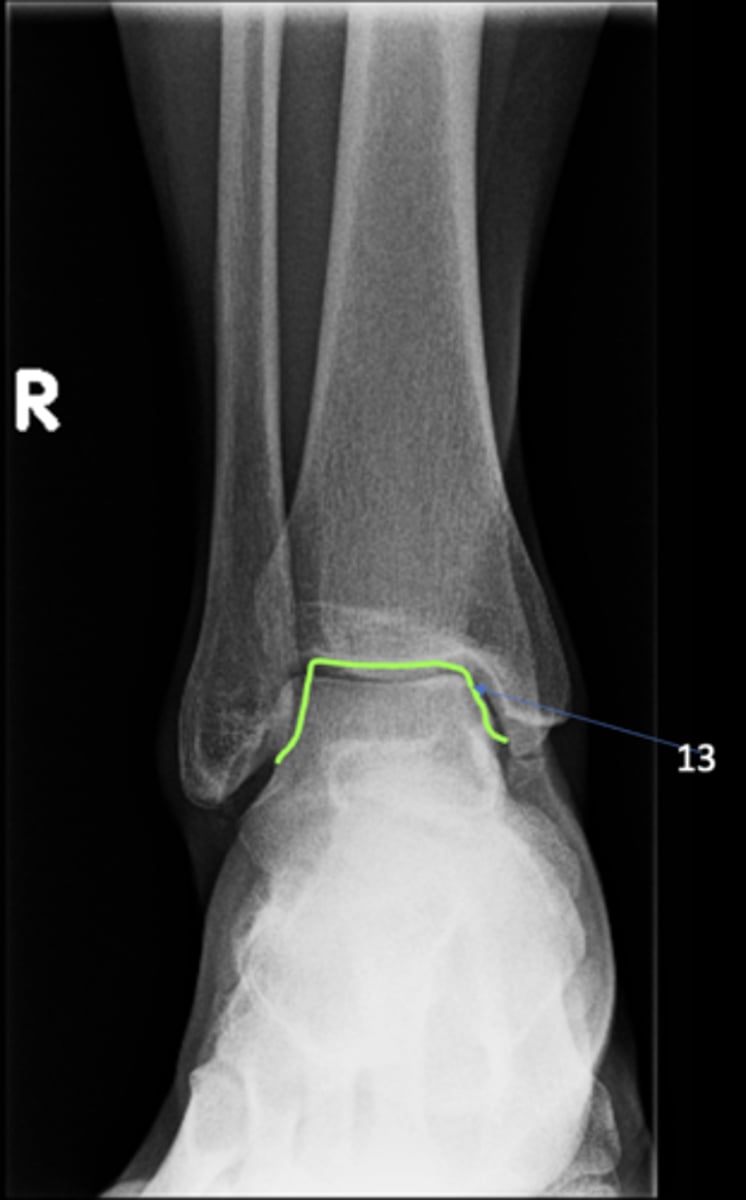

Right AP ankle

View?

<p>View?</p>

ID 11

<p>ID 11</p>

12

New cards

Left femoral neck

ID 12

Tibial plafond

Trochlea of talus

ID 13

Distal tibiofibular joint

ID 14 (joint)

Tibiotalar joint

ID 17 (joint)